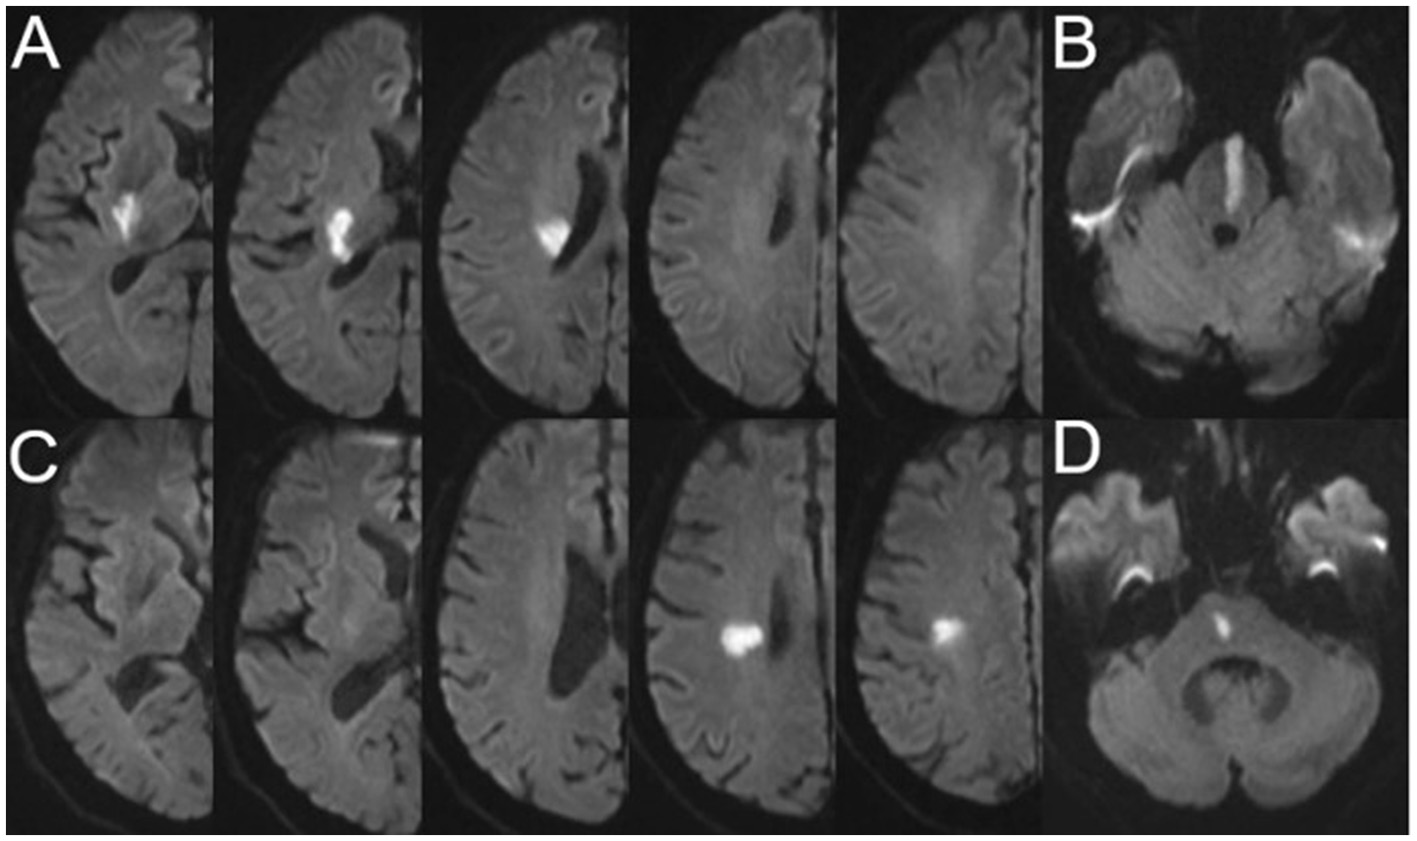

The characteristics of SSI were evaluated using a 3.0T superconducting nuclear magnetic resonance apparatus (Siemens, Germany). Imaging sequences included T1-weighted imaging (T1WI), T2-weighted imaging (T2WI), fluid-attenuated inversion-recovery (FLAIR), and diffusion-weighted imaging (DWI) (slice thickness: 0.8 mm; interval: 0 mm; field of view: 230 mm × 230 mm). The most common parameters used in the imaging sequences were as follows: T1WI: repetition time (TR) = 450 ms, echo time (TE) = 10 ms; T2WI: TR = 4,350 ms, TE = 95 ms; FLAIR: TR = 8,200 ms, TE = 113 ms; and DWI: TR = 4,000 ms, TE = 97 ms. The presence of a single perforating infarction detected by DWI in the supply area of the middle cerebral, vertebral, or basilar artery is referred to as SSI (21). A perforating infarct in the middle cerebral artery was defined as an infarct detected in the supply area of the lenticulostriate arteries, including the basal ganglia (globus pallidus, putamen, thalamus, and caudate), corona radiata, and internal capsule (22). A perforating infarct in the basilar artery was defined as an infarct limited to the paramedian pontine area and in the vertebral artery was defined as an infarct limited to the medial medulla (16). According to previous studies and the positional relationship between the infarct and the parent artery, we classified SSI into proximal SSI (pSSI) and distal SSI (dSSI) (4, 21). pSSI was defined as an infarct that was located adjacent to the parent artery, extending toward the basal surface of the parent artery, whereas dSSI was defined as an infarct that existed only in the distal area of the parent artery (9, 23) (Figure 1).

Figure 1

Representative cases of pSSI and dSSI. (A) pSSI in the anterior circulation; (B) pSSI in the posterior circulation; (C) dSSI in the anterior circulation; and (D) dSSI in the posterior circulation. pSSI, proximal single subcortical infarction; dSSI, distal single subcortical infarction.